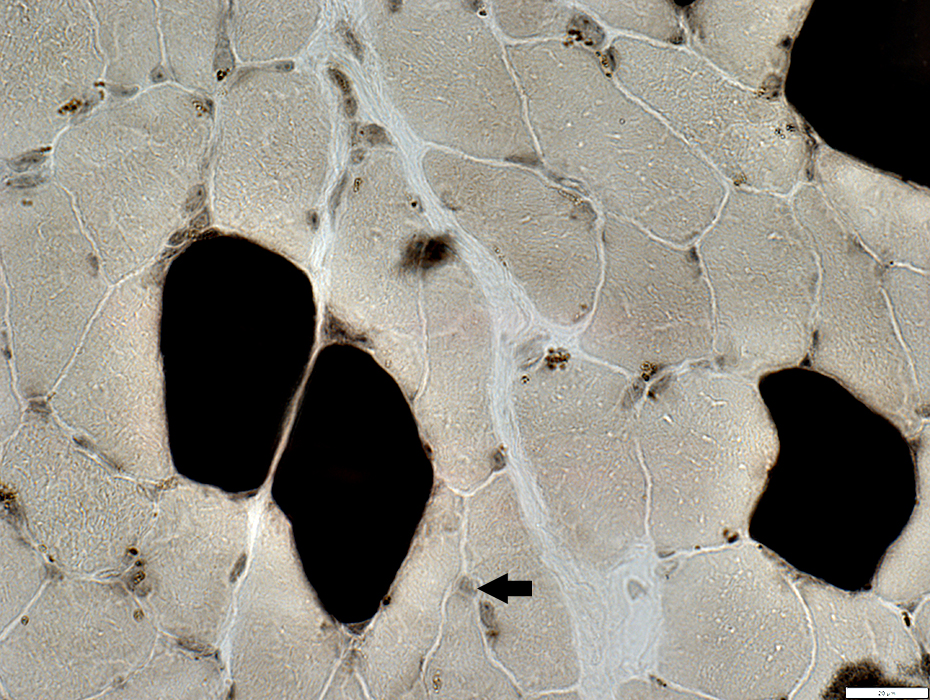

ATPase pH 4.3

Endomysial capillaries

Pale staining by ATPase pH 4.3 (Arrows)

Large size

UEA-I

From: R Schmidt